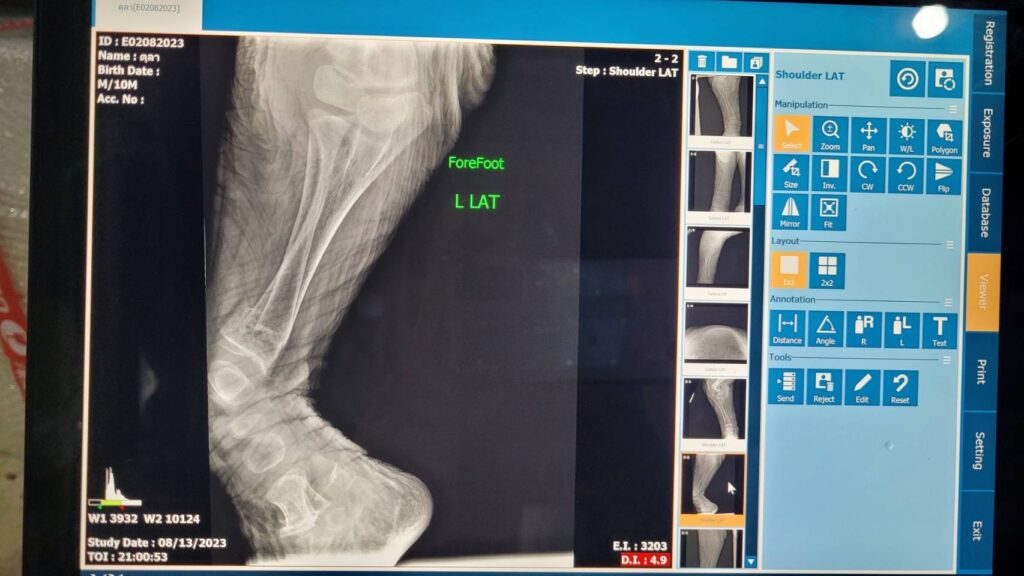

สัตวแพทย์ลงความเห็นเบื้องต้นถึงสาเหตุการล้มว่า เกิดการภาวะบาดเจ็บรุนแรงของกระดูกต้นขาหน้าทั้ง 2 ขา หัก (Humerus fracture) ทำให้เกิดการช็อกตามมา (Pain shock)

ด้านนายเผด็จ ลายทอง ผู้อำนวยสำนักอนุรักษ์สัตว์ป่า ร่วมกับทีมสัตวแพทย์ทำการชันสูตรเพื่อหาสาเหตุและเก็บตัวอย่างส่งตรวจทางปฏิบัติการเพื่อยืนยันถึงสาเหตุการเสียชีวิต ปรากฏว่า สาเหตุหลักในการเสียชีวิต เกิดจากสภาวะกระดูกบางทั่วร่างกาย โดยเฉพาะบริเวณขาหน้า (ด้านบน) ทั้งสองข้าง พบการสลายของกระดูก ทำให้กระดูกแตกหักละเอียด ผิดรูป ซึ่งเป็นสาเหตุของอาการไม่ล้มตัวลงนอน และเล่นกับพี่เลี้ยงตามปกติ อวัยวะภายในร่างกายพบว่า ลำไส้มีความแดงผิดปกติ และสัตวแพทย์ได้ทำการเก็บตัวอย่างอวัยวะทั้งหมด รวมถึงกระดูก ส่งทางห้องปฏิบัติการ คณะสัตวแพทยศาสตร์ มหาวิทยาลัยเกษตรศาสตร์ วิทยาเขตกำแพงแสน คณะสัตวแพทยศาสตร์ จุฬาลงกรณ์มหาวิทยาลัย คณะสัตวแพทยศาสตร์ มหาวิทยาลัยมหิดล และ ศูนย์พัฒนาการทางสัตวแพทย์ภาคตะวันออก กรมปศุสัตว์